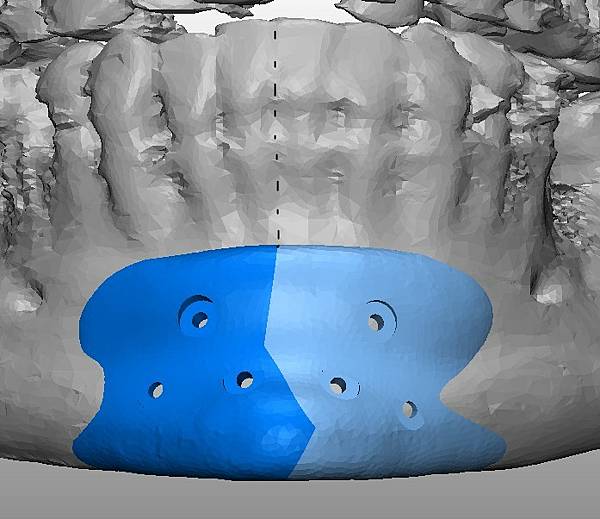

(下圖)3D模擬後工程師版的設計下巴假體的外型。

經過李醫師醫師對客戶外型的判斷,修改工程師的設計,建議更改後的假體模型(下圖)

(上圖)經過李醫師醫師對客戶外型的判斷,修改工程師的設計,建議更改後的假體模型。所以嘍,醫師的美感與專業度必須要做判斷,3D列印只是精準工具但是必須有專業醫師的判斷才可以完美!

下圖: 在李醫師確認後完美精準例印

窄小後縮的下巴,以精準3D列印技術來客製化醫師判斷後的外型下巴假體,一起改善嘴形相對的狀態。

窄小後縮的下巴,以精準3D列印技術來客製化醫師判斷後的外型下巴假體,一起改善嘴形相對的狀態。

3D模擬後 列印出吻合的設計下巴假體